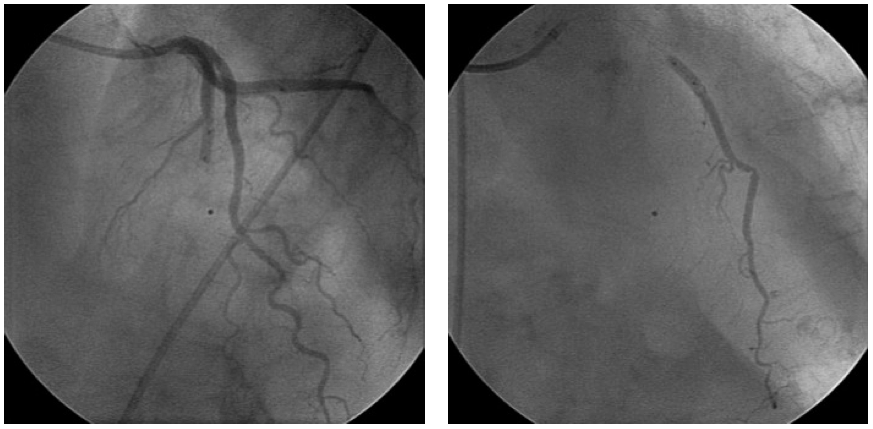

Figure 1. Intracoronary cell delivery using the “stop-flow” technique.

图 1. 利用 “停流” 技术进行冠状动脉内细胞递送。

The left panel demonstrates balloon occlusion at the site of the stented segment.

左图,显示支架段部位球囊阻塞情况。

Contrast injection confirms stop of the flow for the given balloon size at low pressure inflation.

造影剂注射确认,在低压充盈下,给定尺寸的球囊成功阻断血流。

Contrast injection through the internal balloon lumen right panel shows the expected cell distribution when injected during the balloon occlusion.

右图,通过球囊内腔注入造影剂,显示在球囊阻塞期间注入时的预期细胞分布。

A balloon angioplasty OTW catheter is placed at the site of the stented segment at the location of the culprit lesion of the infarct-related coronary artery.

将一个球囊血管成形术 OTW 导管置于支架段所在位置,即梗死相关冠状动脉的罪犯病变处。